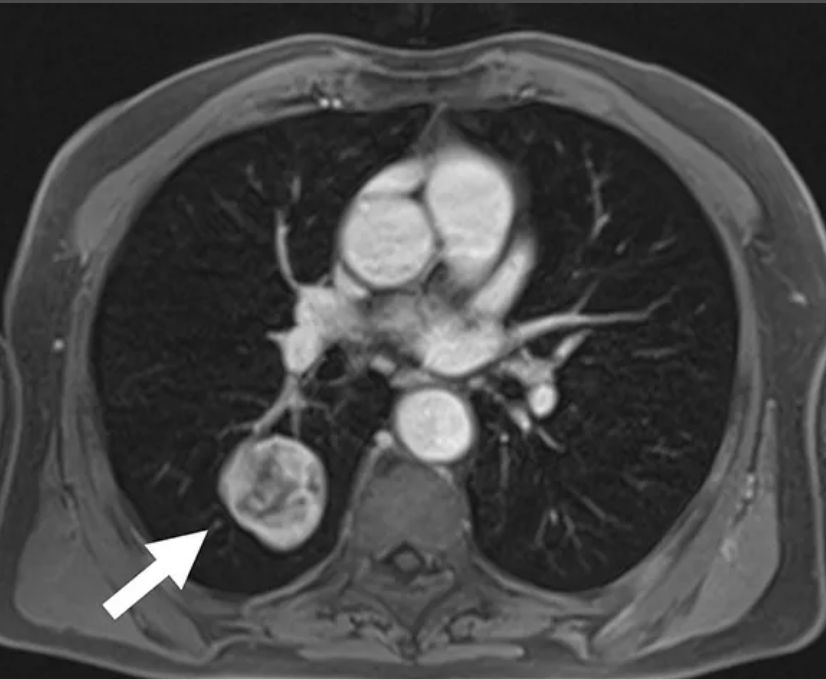

Фотографии и снимки КТ легких без контрастных веществ

Раздел: Визуальный дайджест